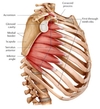

What is this muscle?

What is this muscle?

Latissimus Dorsi